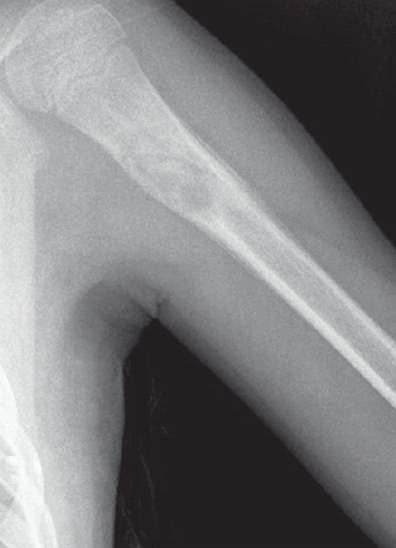

Pisespong Patamasucon, MD; Felicia Lam, MD, MPH

A 15-year-old girl presented with a 2-week history of a mass on the left side of her neck.